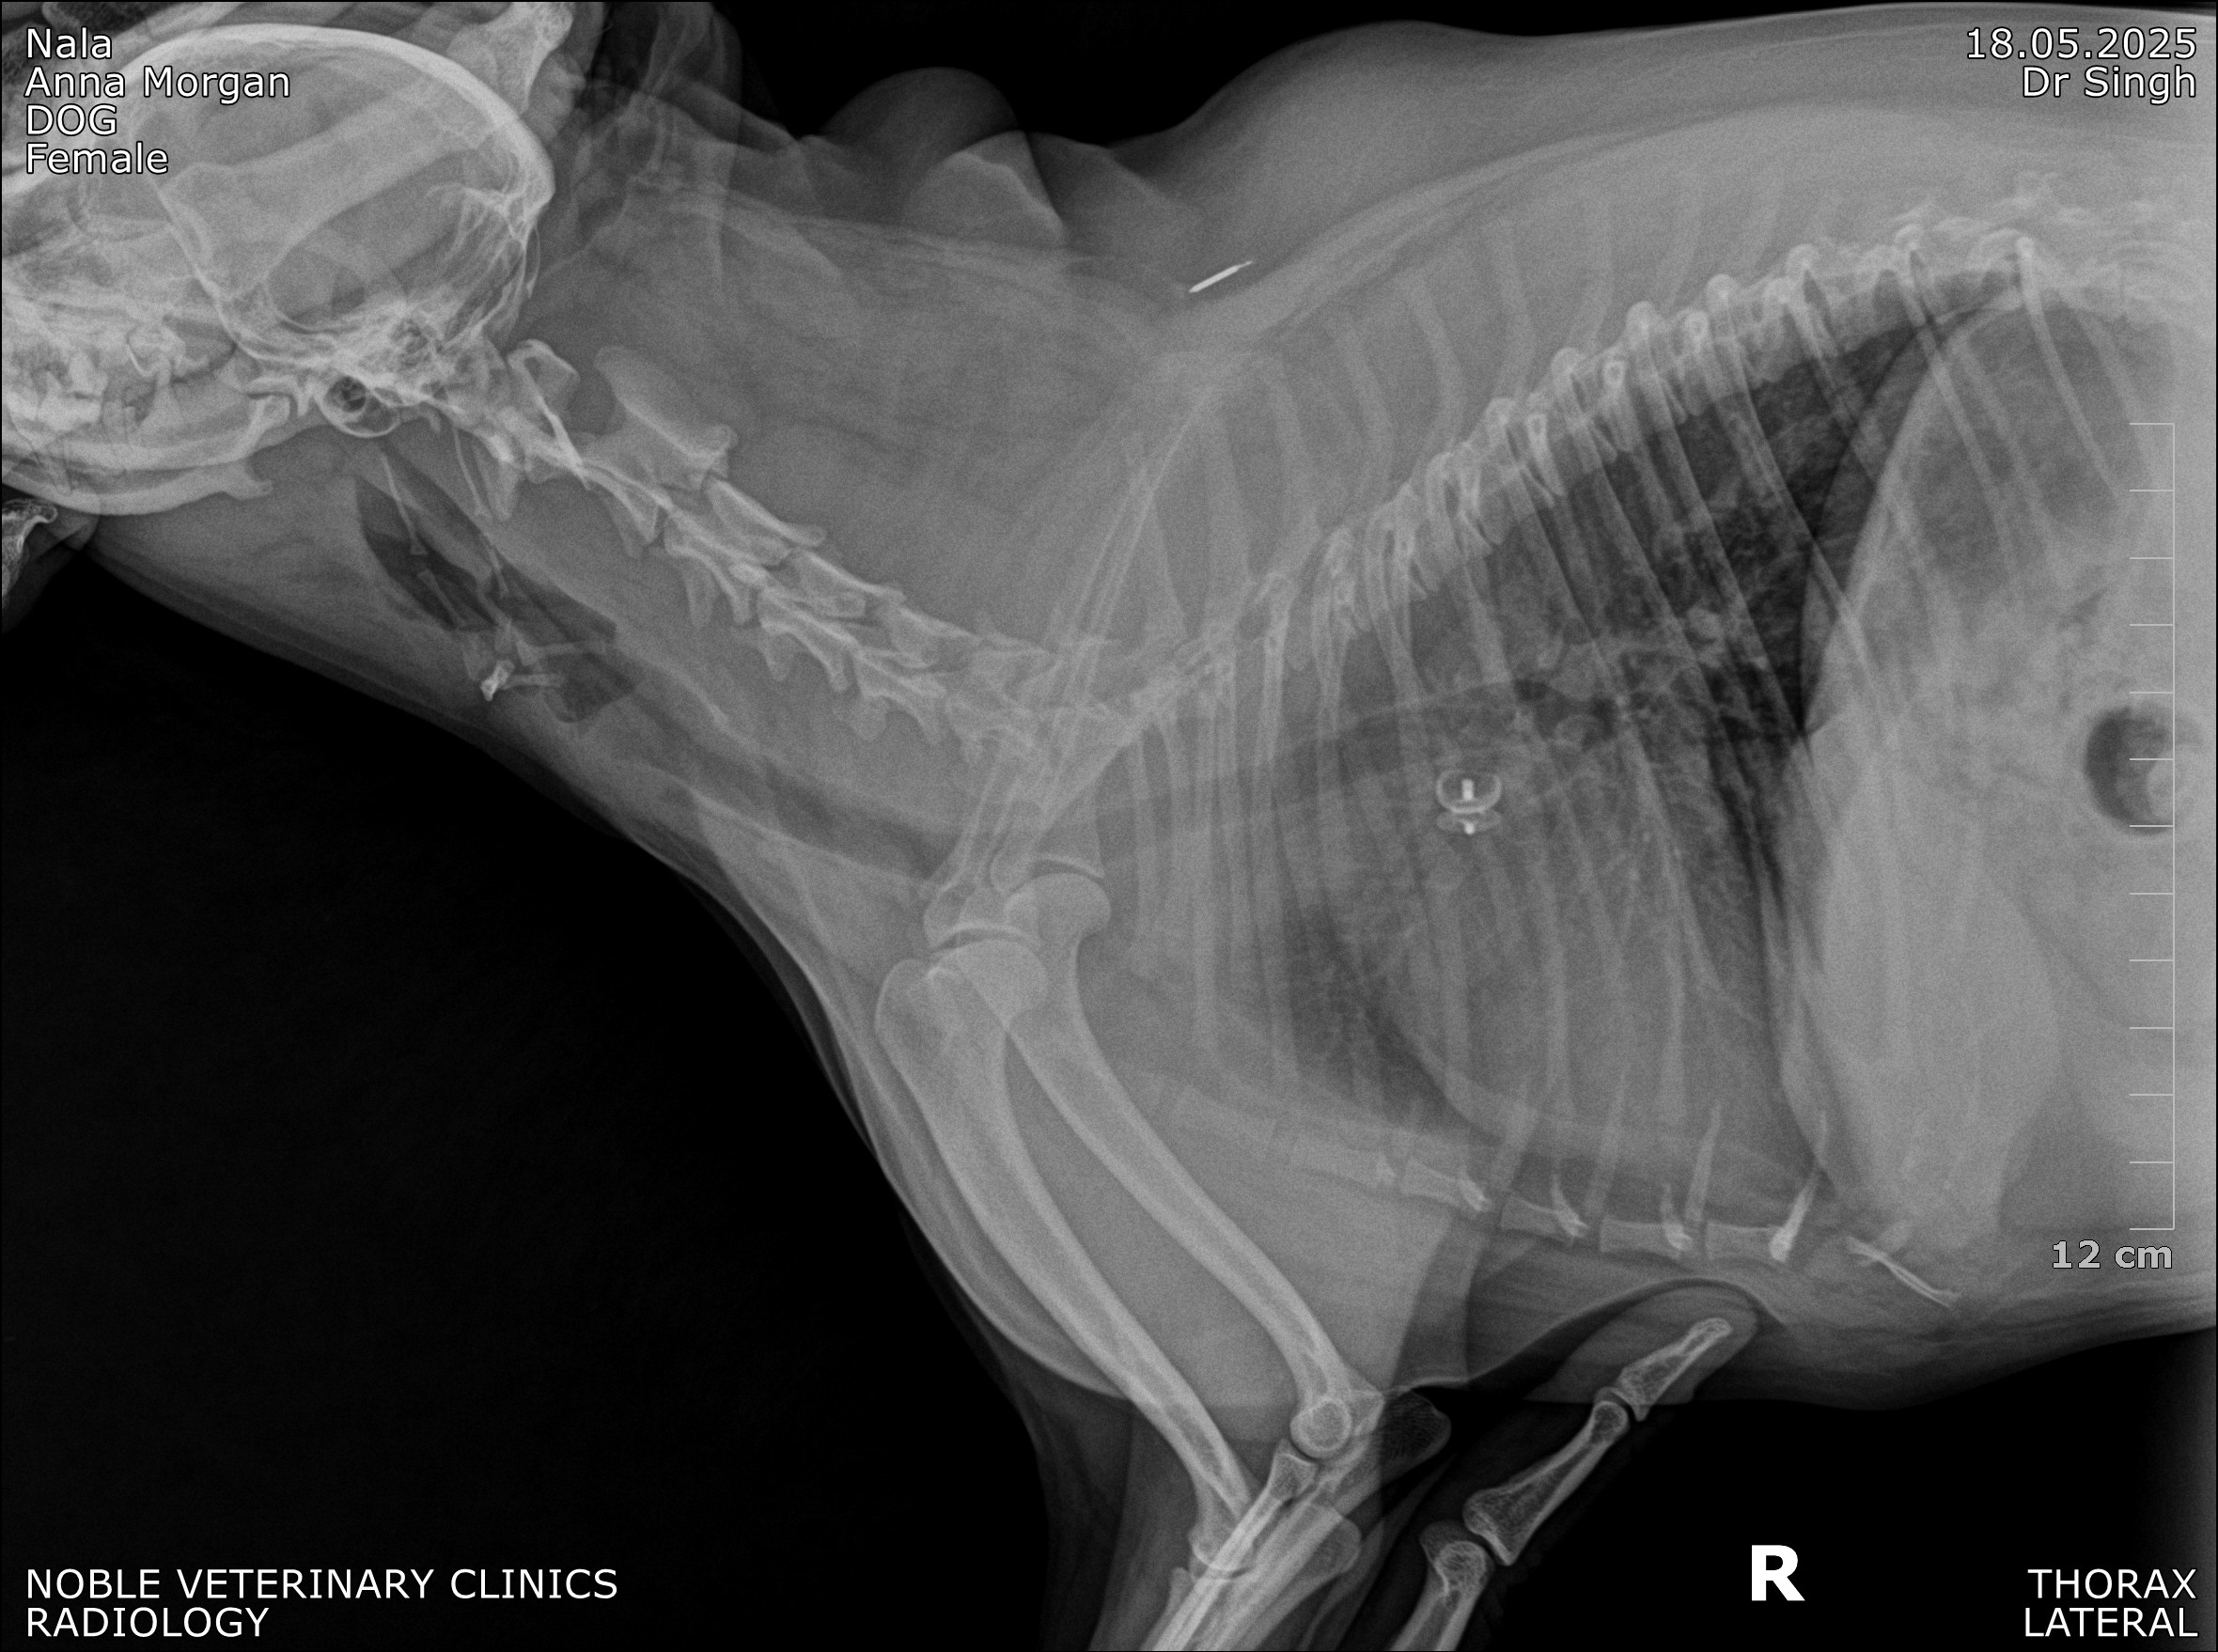

Suspected tracheal collapse. Subtle breathing difficulties. A careful airway examination revealed the true cause: soft palate hyperplasia, corrected surgically to restore Nala’s comfort and energy.

Nala, a 4-year-old Pomeranian, had been struggling with noisy breathing and reduced stamina. Her family was previously told she might have tracheal collapse and even believed she needed surgery for it. Concerned and searching for clarity, they brought Nala to us for a more detailed assessment.

During her examination, it became clear that something didn’t add up. Nala showed none of the typical clinical signs of tracheal collapse. Her breathing pattern suggested another underlying cause, prompting us to investigate further.